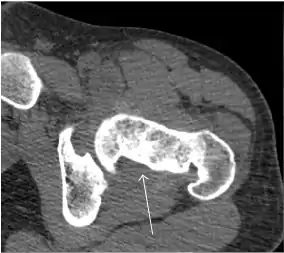

Synovial chondromatosis can be confidently diagnosed by X-ray when calcified cartilaginous chondromas are seen. However, other synovial proliferative processes, such as pigmented villonodular synovitis, require MRI for accurate diagnosis, although noncalcified synovitis can be suspected in radiographs by indirect signs, such as soft tissue swelling and/or erosions in the femoral head, femoral neck, or acetabulum (Figure 7).[1]

Figure 7:

Axial CT image of pigmented villonodular synovitis eroding the posterior cortex of the femoral neck.[1]

CT of synovial chondromatosis.[1]

In synovial proliferative disorders, MRI demonstrates synovial hypertrophy. In the case of PVNS, characteristic foci of low signal intensity related to hemosiderin deposition are better seen on gradient echo T2* images (Figure 7). In the case of synovial osteochondromatosis, the synovial hypertrophy is accompanied by intermediate signal cartilaginous loose bodies and/or low signal calcified loose bodies.[1]